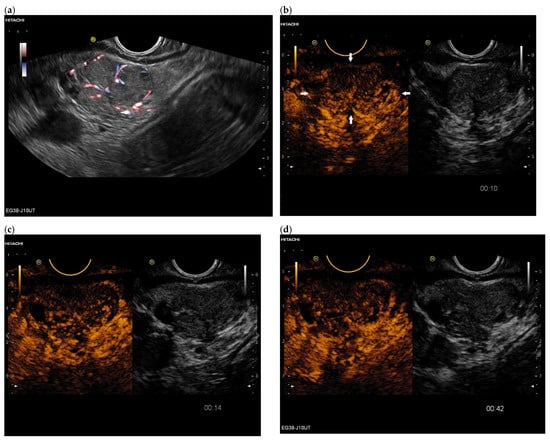

3.4. CEUS and CH-EUS

| Colour Doppler Imaging | RCC metastases are hypervascularized Most other pancreatic metastases are hypovascularized | No hypervascularization | Hypervascularized |

| Cases | CEUS | CH-EUS | ||

|---|---|---|---|---|

| Arterial Phase | Venous Phase | Arterial Phase | Venous Phase | |

| RCC metastases [83] (n = 4) | Hyperenhancement, Early | Hyperenhancement | ||

| RCC metastases [61] (n = 3) | Hyperenhancement, homogeneous pattern | Slow washout | ||

| RCC metastasis [86] (n = 1) | Hyperenhancement, Inhomogeneous pattern | No washout | ||

| Melanoma metastasis [63] (n = 1) | Iso- to slightly hypoenhanced | Hypoenhanced | ||

| Melanoma metastasis [87] (n = 1) | Isoenhanced | Hypoenhancement of the peripheral rim, central non-enhancement | ||

| Melanoma metastasis [61] (n = 1) | Isoenhanced, heterogeneous | Fast washout | ||

| SCLC metastasis [83] (n = 1) | Hyperenhancement | Rapid washout | ||

| Breast, ovarian, colon metastases, sarcoma metastases [61] (n = 6) | Hypoenhancement, homogeneous or heterogeneous | Fast or slow washout | ||

| Lymphoma metastasis [61] (n = 1) | Hyperenhancement, homogeneous pattern | Fast washout |